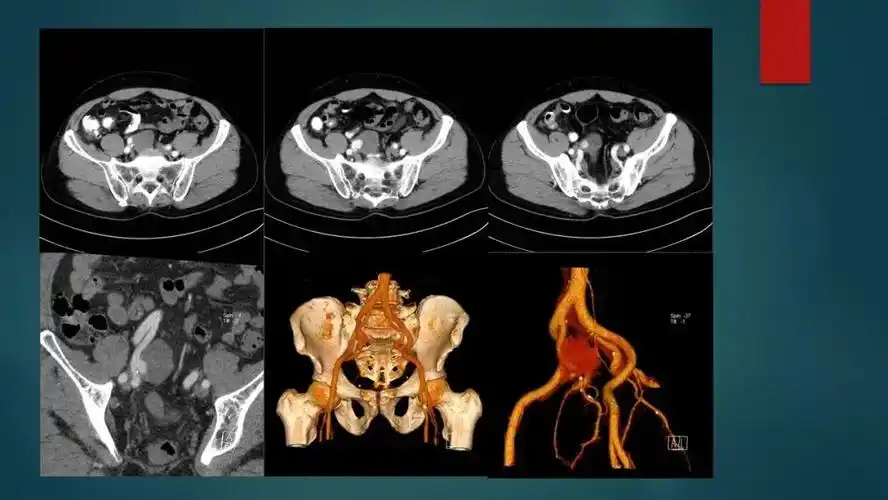

【x121】假性动脉瘤